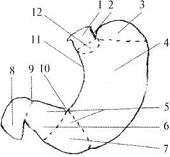

Анатомически в желудке различают: кардиальную часть, свод желудка, тело и привратниковую часть (рис.1.22), малую и большую кривизну, а также переднюю и заднюю стенки. По своей функции желудок подразделяется на секреторный отдел – это кардия и тело желудка, т.е. пищеварительная часть (pars digistorius); экскреторный отдел, соответствующий отделу желудка, выполняющему функцию эвакуации (canalis egestorius), и инкреторный отдел, ограниченный пределами привратника. Кардиальная часть желудка расположена на уровне X-XI грудных позвонков, привратниковая – на уровне I поясничного позвонка.

| Рис. 1.22. Отделы желудка (схема). 1 — oesophagus; 2 — incisure cardialis; 3 — fornix gastrici; 4 — corpus gastricum; 5 — pars pylorica; 6 — canalis pyloricus; 7 — antrum pyloricum; 8 — duodenum; 9 — pylorus; 10 — incisura angularis; 11 — curvatura minor; 12 — pars cardiaca |